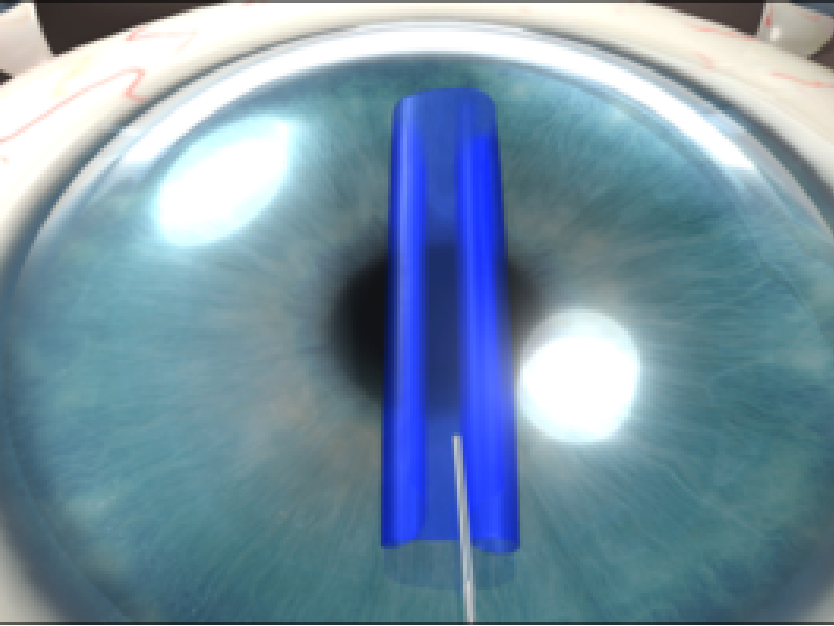

Corneal Remodeling

Parker Cornea provides state-of-the-art procedures for cornea remodeling, including INTACS and CAIRS.